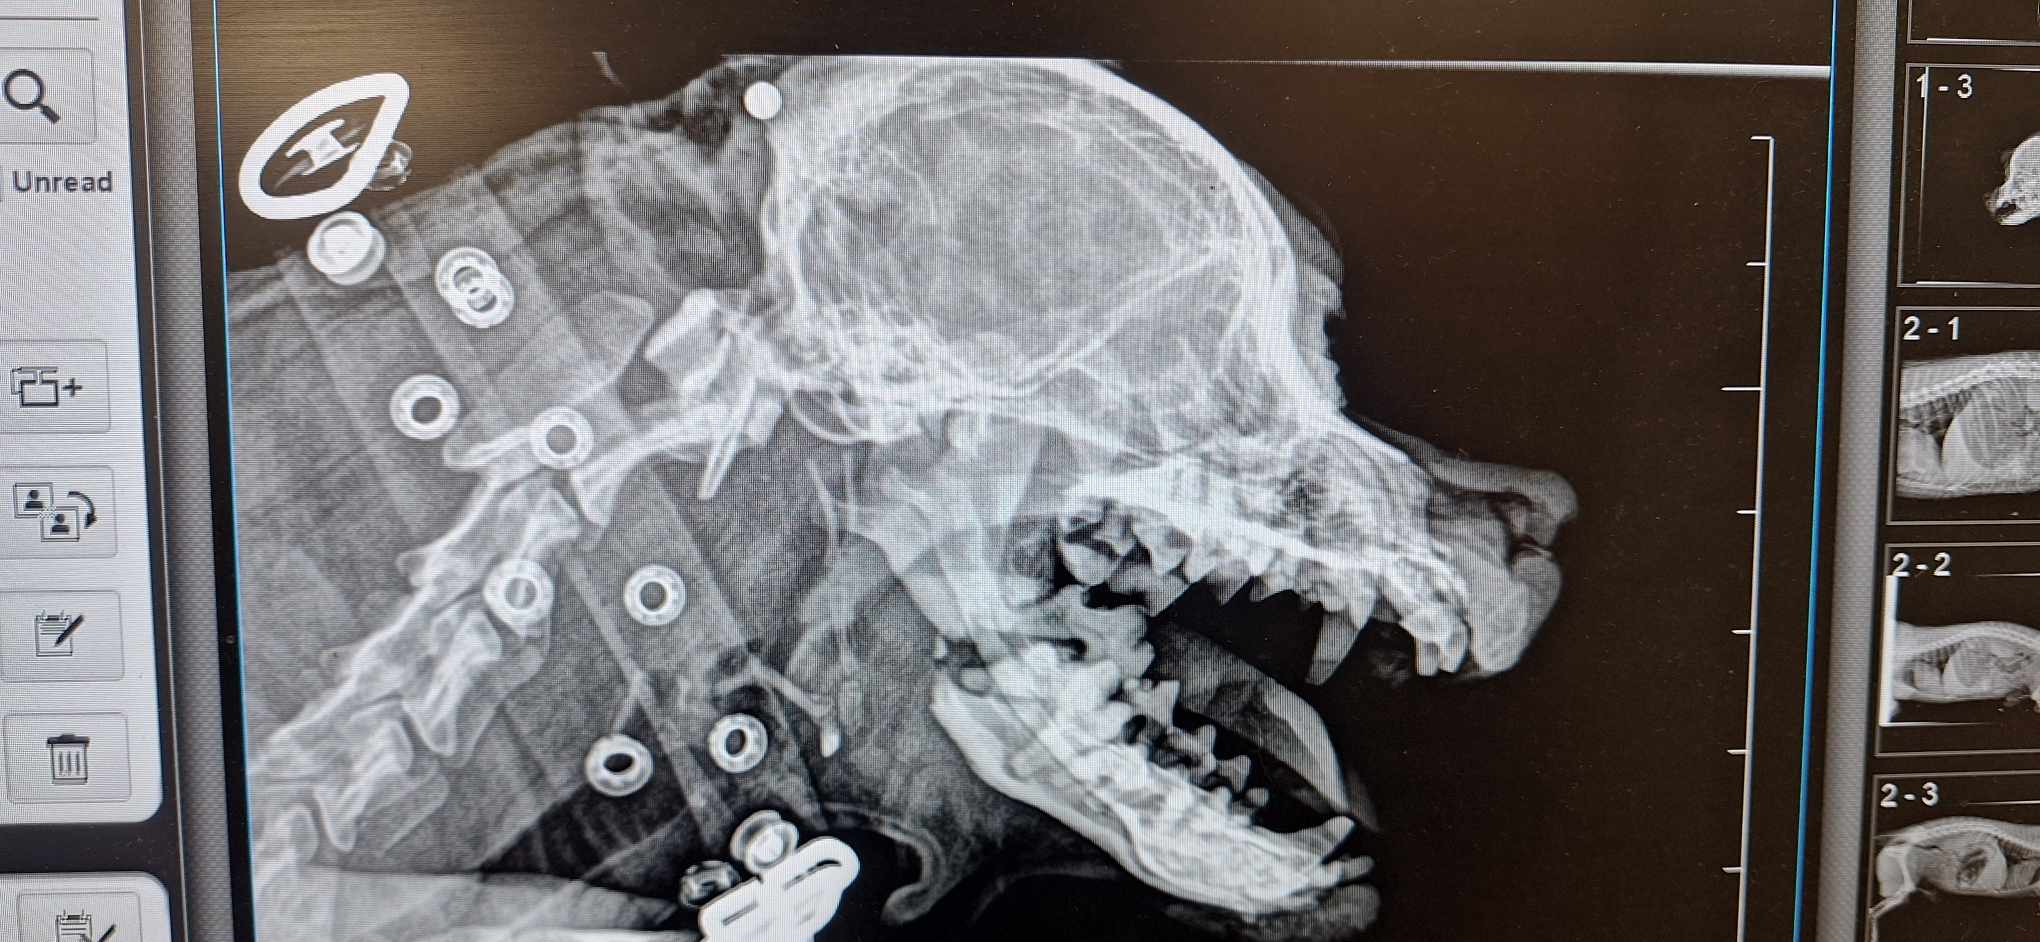

Rentgenas parodė ne tik perlūžusį bei sutrupintą žandikaulį, bet ir pakaušyje įstrigusį šratą, kurio įėjimo anga dar kraujavo… Kažkas šovė į seną mažą šuniuką, kas, galimai, turėjo įtakos įvykusiai nelaimei… Kam užkliuvo, kas toks beširdis?!

Sutvirtintas žandikaulis- ne paskutinė operacija. Dar, kai sugis, teks iš sutrupėjusios apatinio žandikaulio dalies ištraukti dantų šaknų nuolaužas.